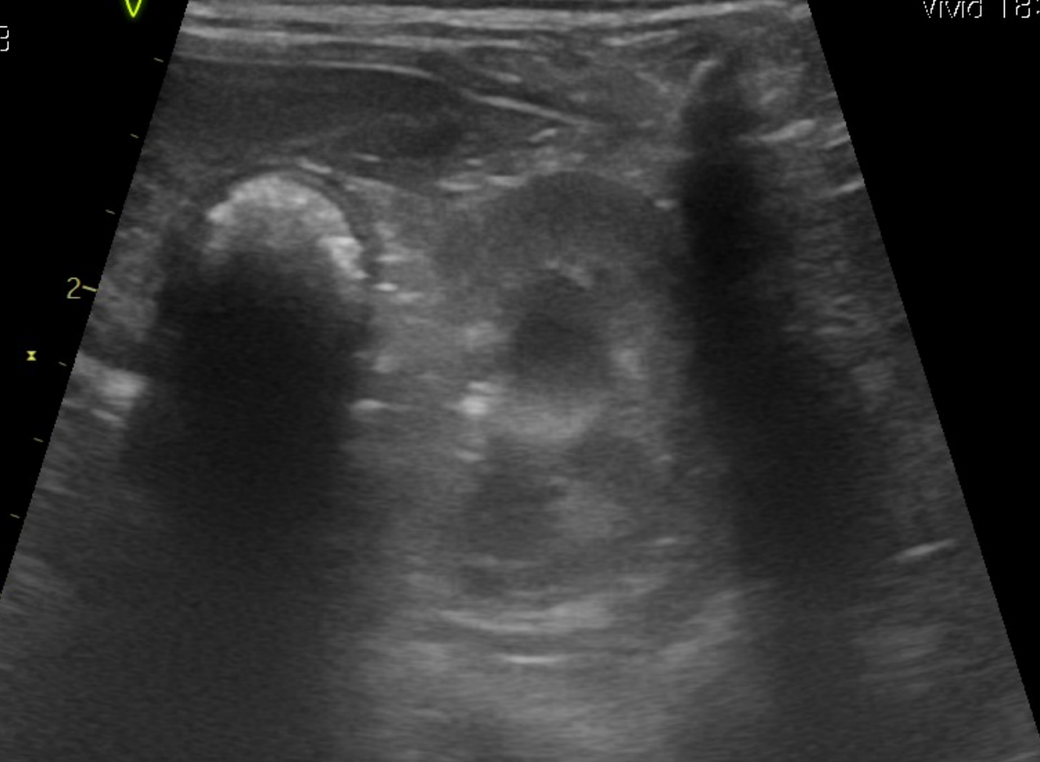

강아지 신장결석 종류 모양만으로는 판단이 안되나요? 소변에선 크리스탈이 발견된게 없다고 합니다

모양만으로 추측 조차 할수가 없는건가요? 한번 봐주시면 감사하겠습니다.

예, 없습니다. 결석이 매우 커진 상태 (몇센치미터 크기 정도)로 커졌을때나 일부 추정되지만 겉면과 내부 코어의 씨앗의 성분은 별도라 이때는 또 성분검사를 해야 하는정도로 부정확합니다.